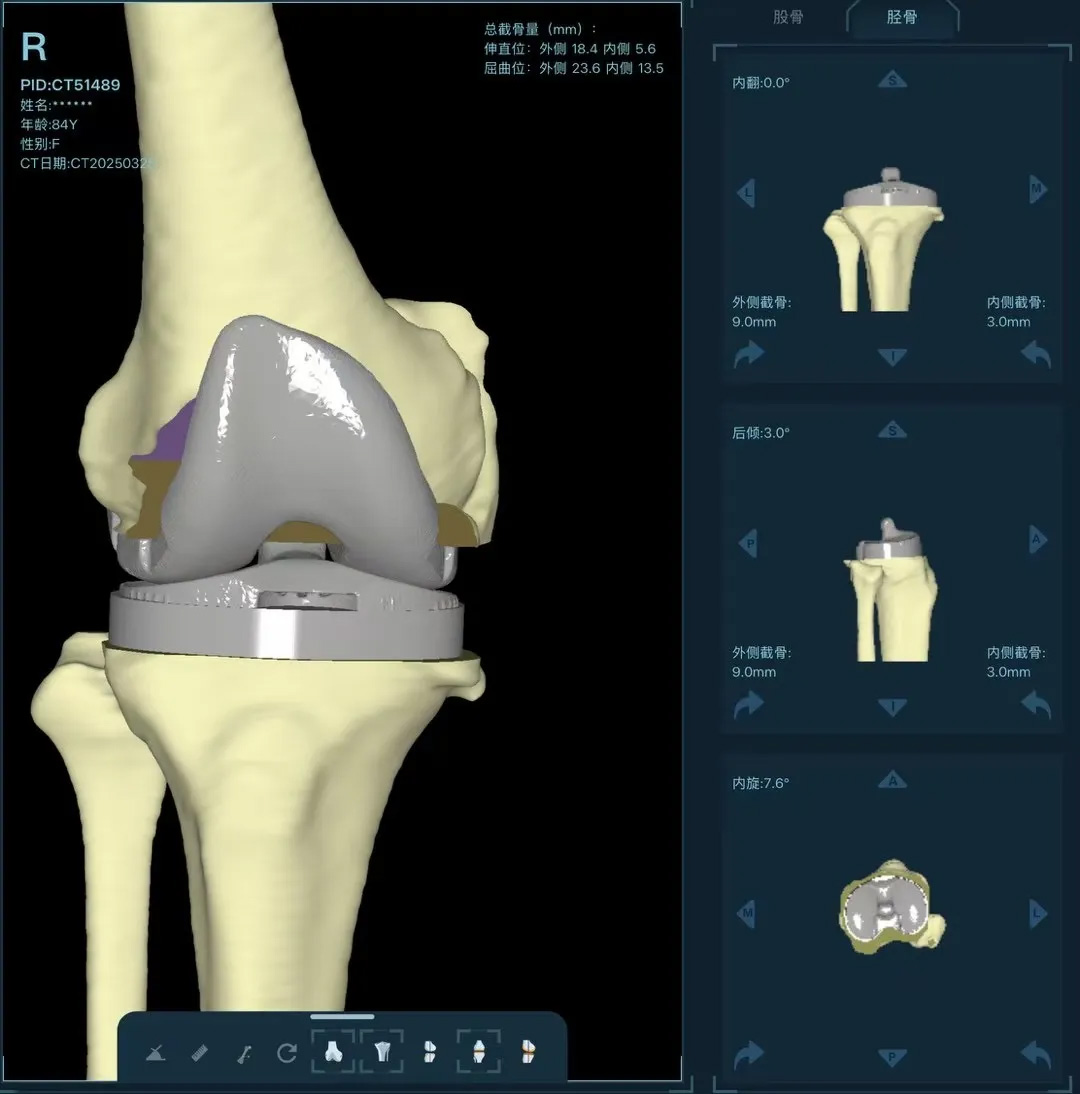

在家人幾乎放棄希望時(shí),AI三維規(guī)劃技術(shù)為這場(chǎng)"關(guān)節(jié)保衛(wèi)戰(zhàn)"帶來(lái)轉(zhuǎn)機(jī)。

術(shù)前:AI通過(guò)CT掃描生成毫米級(jí)膝關(guān)節(jié)三維模型,為假體安裝設(shè)計(jì)出誤差小于1毫米的精準(zhǔn)方案 術(shù)中:智能導(dǎo)航系統(tǒng)如同"透視眼",引導(dǎo)醫(yī)生避開(kāi)密集的神經(jīng)血管網(wǎng),截骨更精準(zhǔn),出血僅100ml 術(shù)后:當(dāng)天鄭阿婆即開(kāi)始抬腿的康復(fù)訓(xùn)練,24小時(shí)內(nèi)扶助行器下地行走,三天后已能在病房走廊獨(dú)立行走,完成洗漱用餐 兩周后健步出院時(shí),女兒含淚感慨“之前擔(dān)心她年紀(jì)大扛不住手術(shù),沒(méi)想到恢復(fù)這么快!現(xiàn)在每天散步比我還精神。知道技術(shù)這么先進(jìn),真該早點(diǎn)來(lái)!”

"這就像給傳統(tǒng)手術(shù)裝上了自動(dòng)駕駛系統(tǒng)。"主刀醫(yī)生羅軍副院長(zhǎng)用生動(dòng)比喻解析技術(shù)突破。AI不僅實(shí)現(xiàn)假體“量身定制”,使用壽命可達(dá)20年以上,更通過(guò)三維路徑規(guī)劃將康復(fù)周期壓縮,實(shí)現(xiàn)術(shù)后24小時(shí)下地,2周回歸正常生活。同時(shí),AI會(huì)避開(kāi)重要組織,具有出血少、感染風(fēng)險(xiǎn)低的特點(diǎn)。專(zhuān)家特別提醒,當(dāng)出現(xiàn)夜間持續(xù)性關(guān)節(jié)疼痛、步行能力低于10分鐘或關(guān)節(jié)畸形時(shí),應(yīng)及時(shí)就醫(yī)評(píng)估,"別等到關(guān)節(jié)'報(bào)廢'才手術(shù)"。